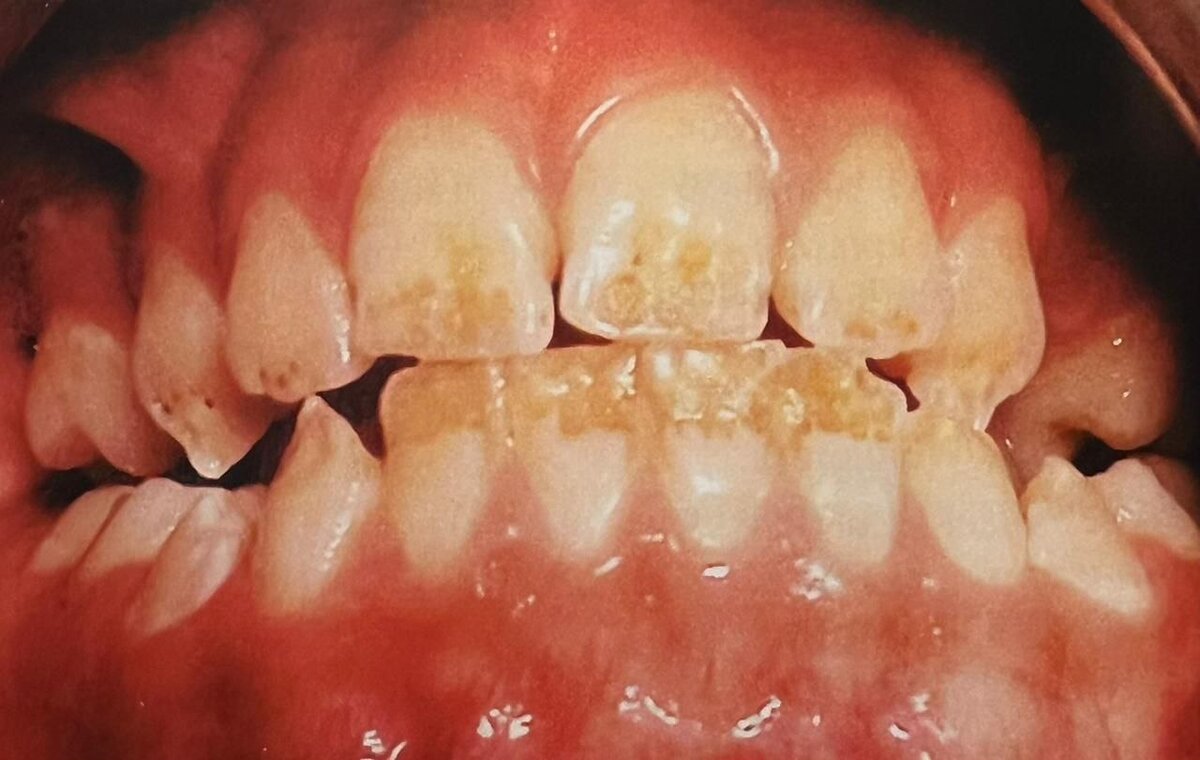

Гипоплазия эмали — это недоразвитие эмали временных или постоянных зубов из-за нарушения обмена веществ в период их развития. Может проявиться во временном или постоянном прикусе. Причины возникновения. Может быть связано с нарушениями внутриутробного развития, воздействием различных патогенов, недостаточным питанием, плохой экологией, общими заболеваниями матери или ребенка. При вынашивании плода: * токсикозы;